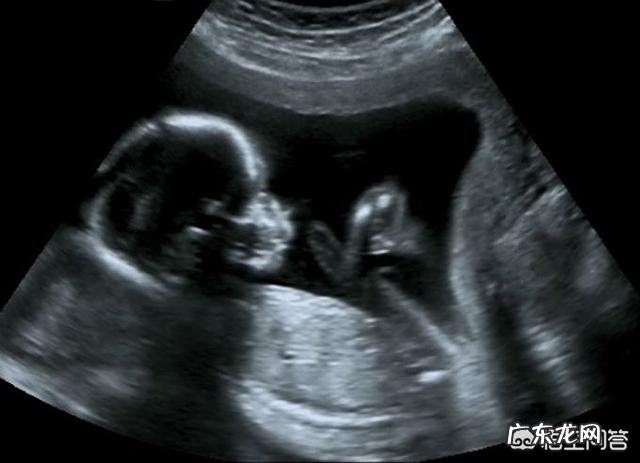

很多人都知道,孕妈怀宝宝,到了差不多快12周的时候,都需要给宝宝做一个筛查,即所谓的“唐氏检查”,这个检查的目的,就是为了判断,宝宝是不是存在先天智力不好,如果真的有问题,那么宝宝以后的路,也就彻底断了,为了达到优生的目的,这种智力有问题的宝宝,是不允许出生的 。所以,通过这个时候的筛查,可以发现宝宝的面部,一般会有一些异常,特别是五官长相方面,多少会表现出异样,这个通过B超,可以很好地发现问题 。

文章插图